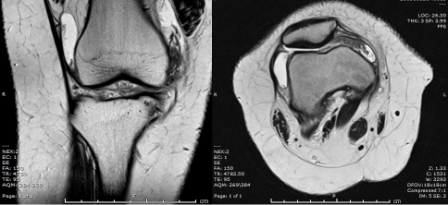

MRI of the knee was performed.

Q. What is your opinion on the MRI scan?

Knee joint effusion

Hypertrophy of the synovium

Normal cartilage and bony outline. Meniscus, ACL, and PCL were intact.